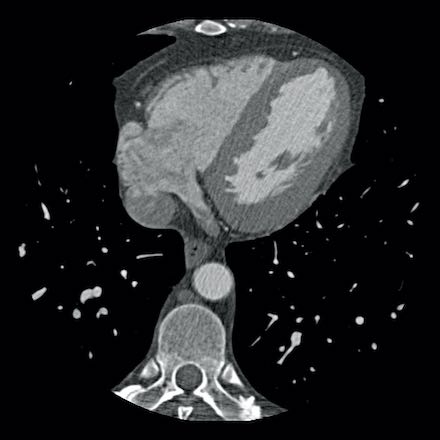

case 2 – CAD-RADS 5/P2/S

First, scroll through the CTA images.

How would you describe the findings on the coronary CTA?

The findings are:

- Stent in the mid

LAD with low-attenuation within the stent suggestive of minimal in-stent

restenosis (<25%). Non-calcified plaque distal to the stent

causing mild stenosis (25-49%). Notice bridging on a short segment in

the distal LAD. - Non-calcified

plaque in the LCX causing mild stenosis (25-49%). - Occlusion of the

proximal OM1 branch with distal filling. - Calcified and

non-calcified plaques in the proximal RCA causing mild (25-49%) stenosis. - Total plaque burden

is moderate based on SIS (four segments including proximal RCA, mid LAD, prox

LCX and OM1).

Due to the occlusion of OM1 branch and presence of the stent, this case

reads as CAD-RADS 5/P2/S, which means that this patient needs further

diagnostic workup.